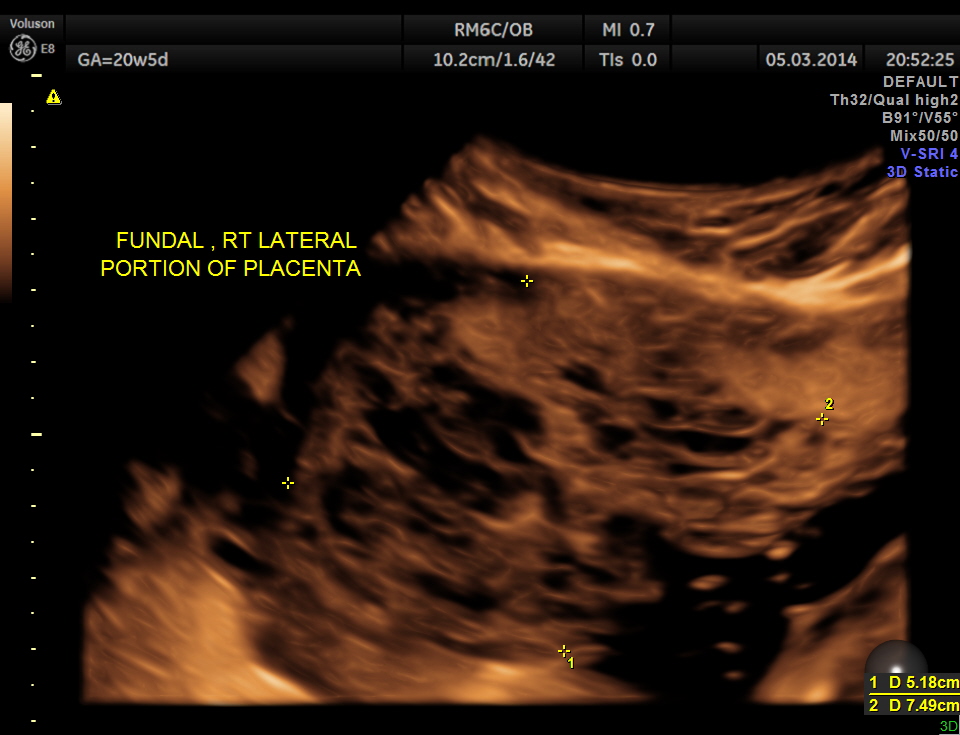

The placenta was on the anterior wall and the scan showed a distinct mass lesion in the antero right lateral portion. The placenta had multiple small cystic appearance in the right lateral aspect . Colour doppler showed no increased vascularity.

She came again after 2 months .The placenta appeared nearly the same , but showed more vascularity.